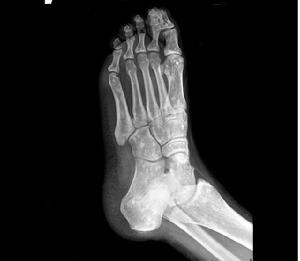

脆弱性骨硬化X線表現 可見圓形或卵子圓形的緻密斑點,幾乎波及全身,特別是在長骨的骨骺部位及乾骺端,但骨幹很少有斑點。斑點的大小不一,直徑大約由2mm~10mm數目不等。在脊柱、肋骨及鎖骨均少見,在顱骨更稀有。骨骼的輪廓改變,骨骺發育亦無影響,關節間隙正常。在成人,斑點一般不再有明顯變化,而在兒童則斑點可以增加,消失及融合。

(4)病灶多累及長骨的兩端,密集於乾骺端及骨骺,以及骨盆、手、足及不規則骨。越靠近關節病灶越密集,且密度越濃。病灶可相互融合成片而遮蓋正常骨組織。

脆弱性骨硬化1、X 線檢查是發現和診斷本病的主要依據。X 線上病灶呈瀰漫多發的圓形、類圓形或融合成條狀及團塊狀緻密影,位於骨松質內,走行與骨長軸一致,雙側基本對稱,大小在數毫米至2 cm 之間;越靠近關節病灶越密集密度也越高;絕大多數病灶中心密度高邊緣密度低,也有少數病灶中心密度偏低,但其邊緣均較清楚;病灶不侵犯骨膜及關節軟骨,關節間隙清晰。